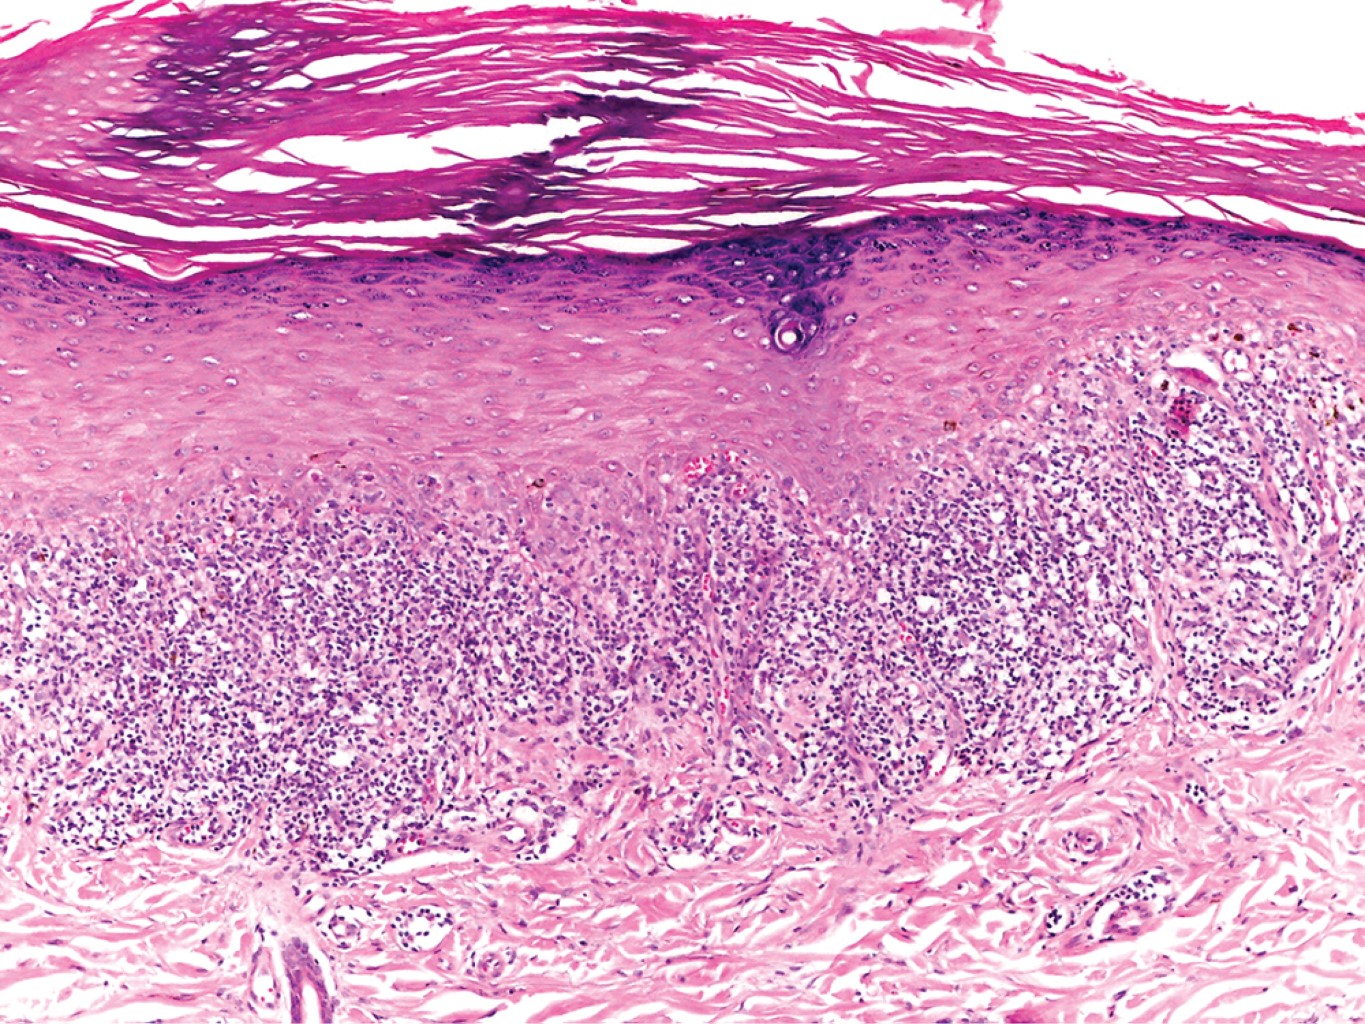

Se realizó biopsia incisional en una de las placas, la cual reportó epidermis con hiperqueratosis ortoqueratósica, tapones córneos, hipergranulosis focal, zonas con acantosis irregular moderada que alternan con áreas de atrofia y degeneración hidrópica de la capa basal con formación de cuerpos coloides; en dermis superficial vasos dilatados e infiltrado moderadamente denso dispuesto en banda constituido por linfocitos, histiocitos y algunos melanófagos (Figuras 2 y 3).

HISTOPATOLOGíA

La migración de las células T CD8+ activadas da como resultado la muerte de queratinocitos basales debido a los efectos combinados del interferón-gamma (IFN-γ), interleucina 6 (IL), factor estimulante de colonias de granulocitos-macrófagos (GM-CSF) y el factor de necrosis tumoral alfa (TNF-α). Las características histopatológicas típicas del liquen plano dependen de la interacción variable entre la degeneración y licuefacción de las células basales y la regeneración epidérmica irregular. El primer cambio identificable en el LP es la presencia de cuerpos coloides y la incontinencia del pigmento asociada. Los cuerpos coloides, citoides o cuerpos de Civatte son estructuras redondas u ovaladas, homogéneas, con eosinófilos identificables dentro del epitelio basal y la dermis papilar, muestran positividad con el ácido periódico de Schiff (PAS), resistente a la diastasa, y pueden identificarse dentro de las pápulas, piel perilesional e incluso piel aparentemente no afectada. En el ámbito ultraestructural, los cuerpos citoides están compuestos por agregados de filamentos de 6 a 8 nm de diámetro, constituidos por queratina, bien ubicados.8

Las características histopatológicas de una pápula antigua son: hiperqueratosis, hipergranulosis en forma de cuña (que se manifiesta clínicamente como estrías de Wickham) relacionadas con los componentes intraepidérmicos de los conductos sudoríparos y los folículos pilosos, y acantosis irregular. Ésta a menudo tiene apariencia en "dientes de sierra". En ocasiones se pueden observar linfocitos e histiocitos en la epidermis, y ocasionalmente necrosis de células satélite, lo cual es característico del padecimiento, así como la degeneración y licuefacción de la capa basal del epitelio. Suelen observarse hendiduras subepidérmicas (espacios de Max Joseph). La incontinencia del pigmento también es frecuente. La dermis superior se encuentra ocupada por infiltrado linfo-histiocitario en banda, lo cual oscurece la unión dérmica-epidérmica. Es posible ver eosinófilos. La hiperqueratosis persiste aun cuando el LP ha remitido y la acantosis retrocede, dando una imagen de aplanamiento de la epidermis. En esta fase, puede haber cicatrices focales y el infiltrado dérmico es menos visible. Las lesiones pueden volverse completamente atróficas con un número variable de cuerpos coloides e incontinencia del pigmento, casi sin inflamación. Si hay escasos cuerpos coloides, la diferencia con la poiquilodermia puede ser muy difícil. En las lesiones de liquen plano anular, las características histológicas típicas sólo se ven en la periferia, en el borde activo de las lesiones.8